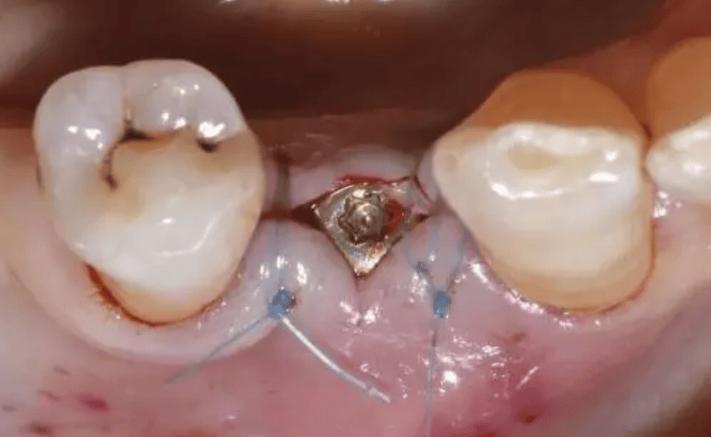

(图片来源网络,侵删)- 可吸收缝线: 这是最常用的种植牙手术缝合材料,这种缝线会在体内逐渐被吸收(通常在1-4周内),不需要专门拆线,医生在手术时使用可吸收线,术后你几乎感觉不到它的存在,它会自行消失。这是目前种植牙手术的主流选择。

- 不可吸收缝线: 少数情况下,医生可能会使用不可吸收的丝线或尼龙线,这种缝线需要按时拆除,否则会长期留在口腔内,可能刺激组织或成为细菌滋生的温床。

- 简单种植: 如果是单颗牙种植,手术创伤相对较小,使用可吸收线的话,通常在术后7-10天左右缝线基本吸收完毕,组织愈合良好。

- 复杂种植: 如果手术涉及植骨、上颌窦提升、使用引导骨再生膜等复杂操作,伤口范围更大、更复杂,愈合时间可能需要更长,缝线吸收或拆除时间可能会延长到10-14天甚至更久。